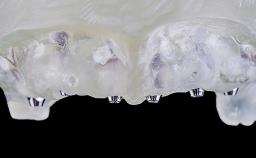

Rehabilitating an Edentulous Maxilla with a Fixed Dental Prosthesis Using a DSD-Guided Approach

A 60-year-old man was referred to the Center of Excellence for Prosthodontics and Implant Dentistry (CEPI) of the School of Dentistry of the University of São Paulo, Brazil for implant therapy. Anamnesis, clinical examination, and radiographs revealed esthetic and functional problems, the absence or structural compromise of various teeth (16–11, 21, 22, 24, 25, 37, 45, and 48), periodontal and endodontic problems (17 and 27), implant fracture (46), and occlusal disorders . The patient reported that he was undergoing treatment for cardiovascular diseases.

Prosthesis Type FDP